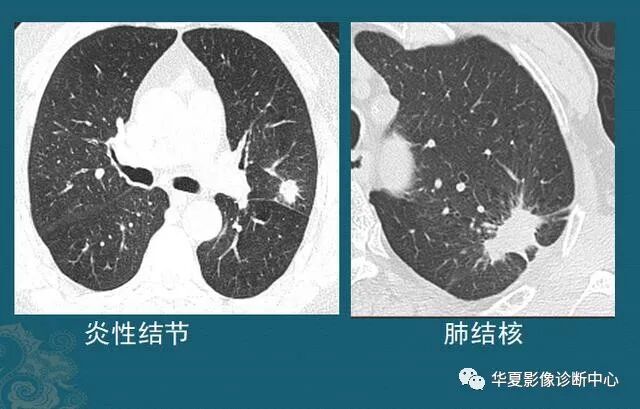

炎症或肺结核,形成小结节,有些可吸收